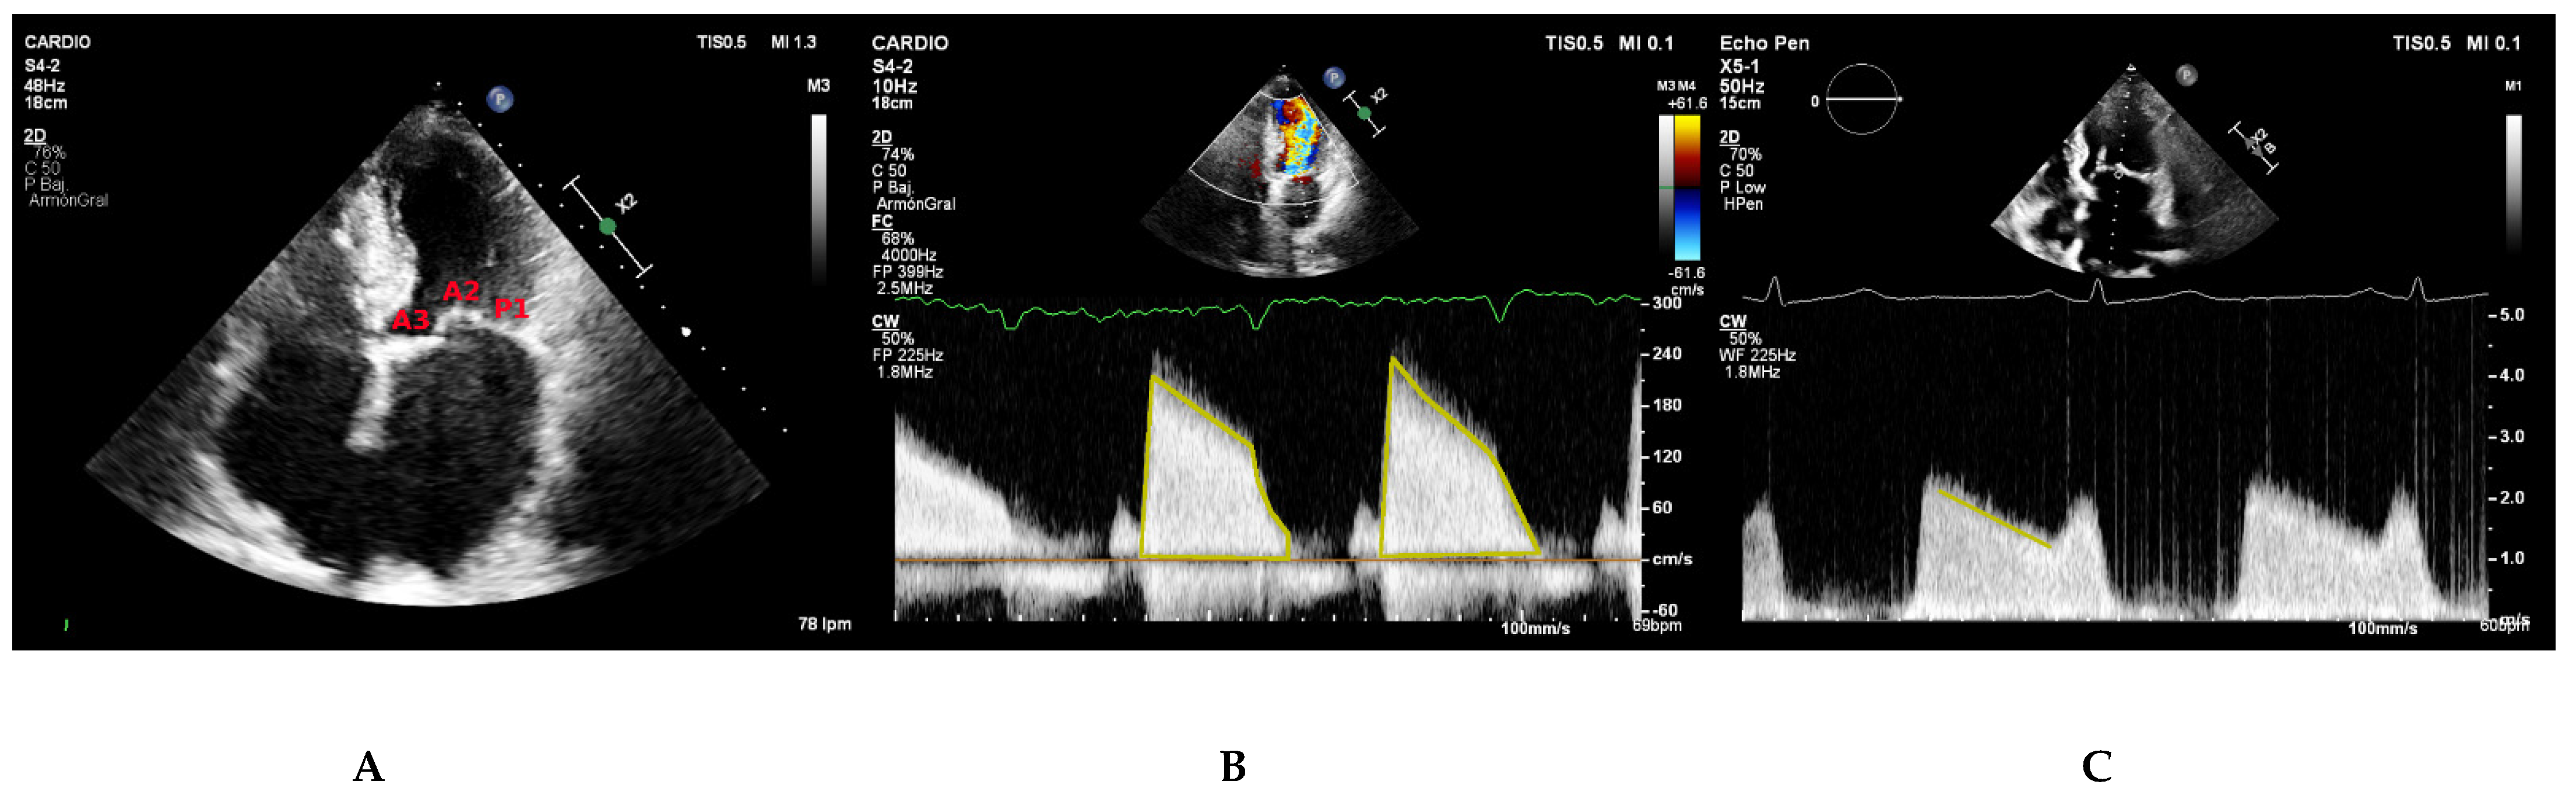

2.2.2. Mitral Gradients

2.2.3. Additional Parameters

5.2. Parasternal Short-Axis View

5.3. Apical Four Chamber View

5.4. Classification of Mitral Stenosis Severity

5.5. Assessment of Feasibility of Percutaneous Mitral Commissurotomy